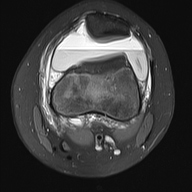

轴位PD序列

脂肪抑制序列

轴位

T1加权像

关节内大量积血,可见血细胞比容增高征。股骨外侧髁前部及髌骨内侧可见挫伤性微骨折。髌骨内侧支持带及髌股内侧韧带水肿增厚。髌骨内侧关节面下关节软骨浸润,提示I期骨软骨损伤。

髌骨外侧隐窝可见游离体,其信号强度与关节软骨一致,提示髌骨关节软骨外剥离损伤。股骨滑车和股骨关节软骨正常。

胫骨近端和腓骨骨骺以及股骨远端延伸至干骺端的骨骺周围可见局灶性骨髓水肿。这些提示存在局灶性骨骺周围水肿区。

十字韧带和侧副韧带正常。半月板正常。股四头肌腱和髌腱正常。

该病例具有短暂性髌骨外侧脱位复位损伤的特征性表现,包括预期的骨挫伤模式、内侧髌骨支持带/内侧髌股韧带损伤、髌骨骨软骨损伤以及髌骨软骨游离体。